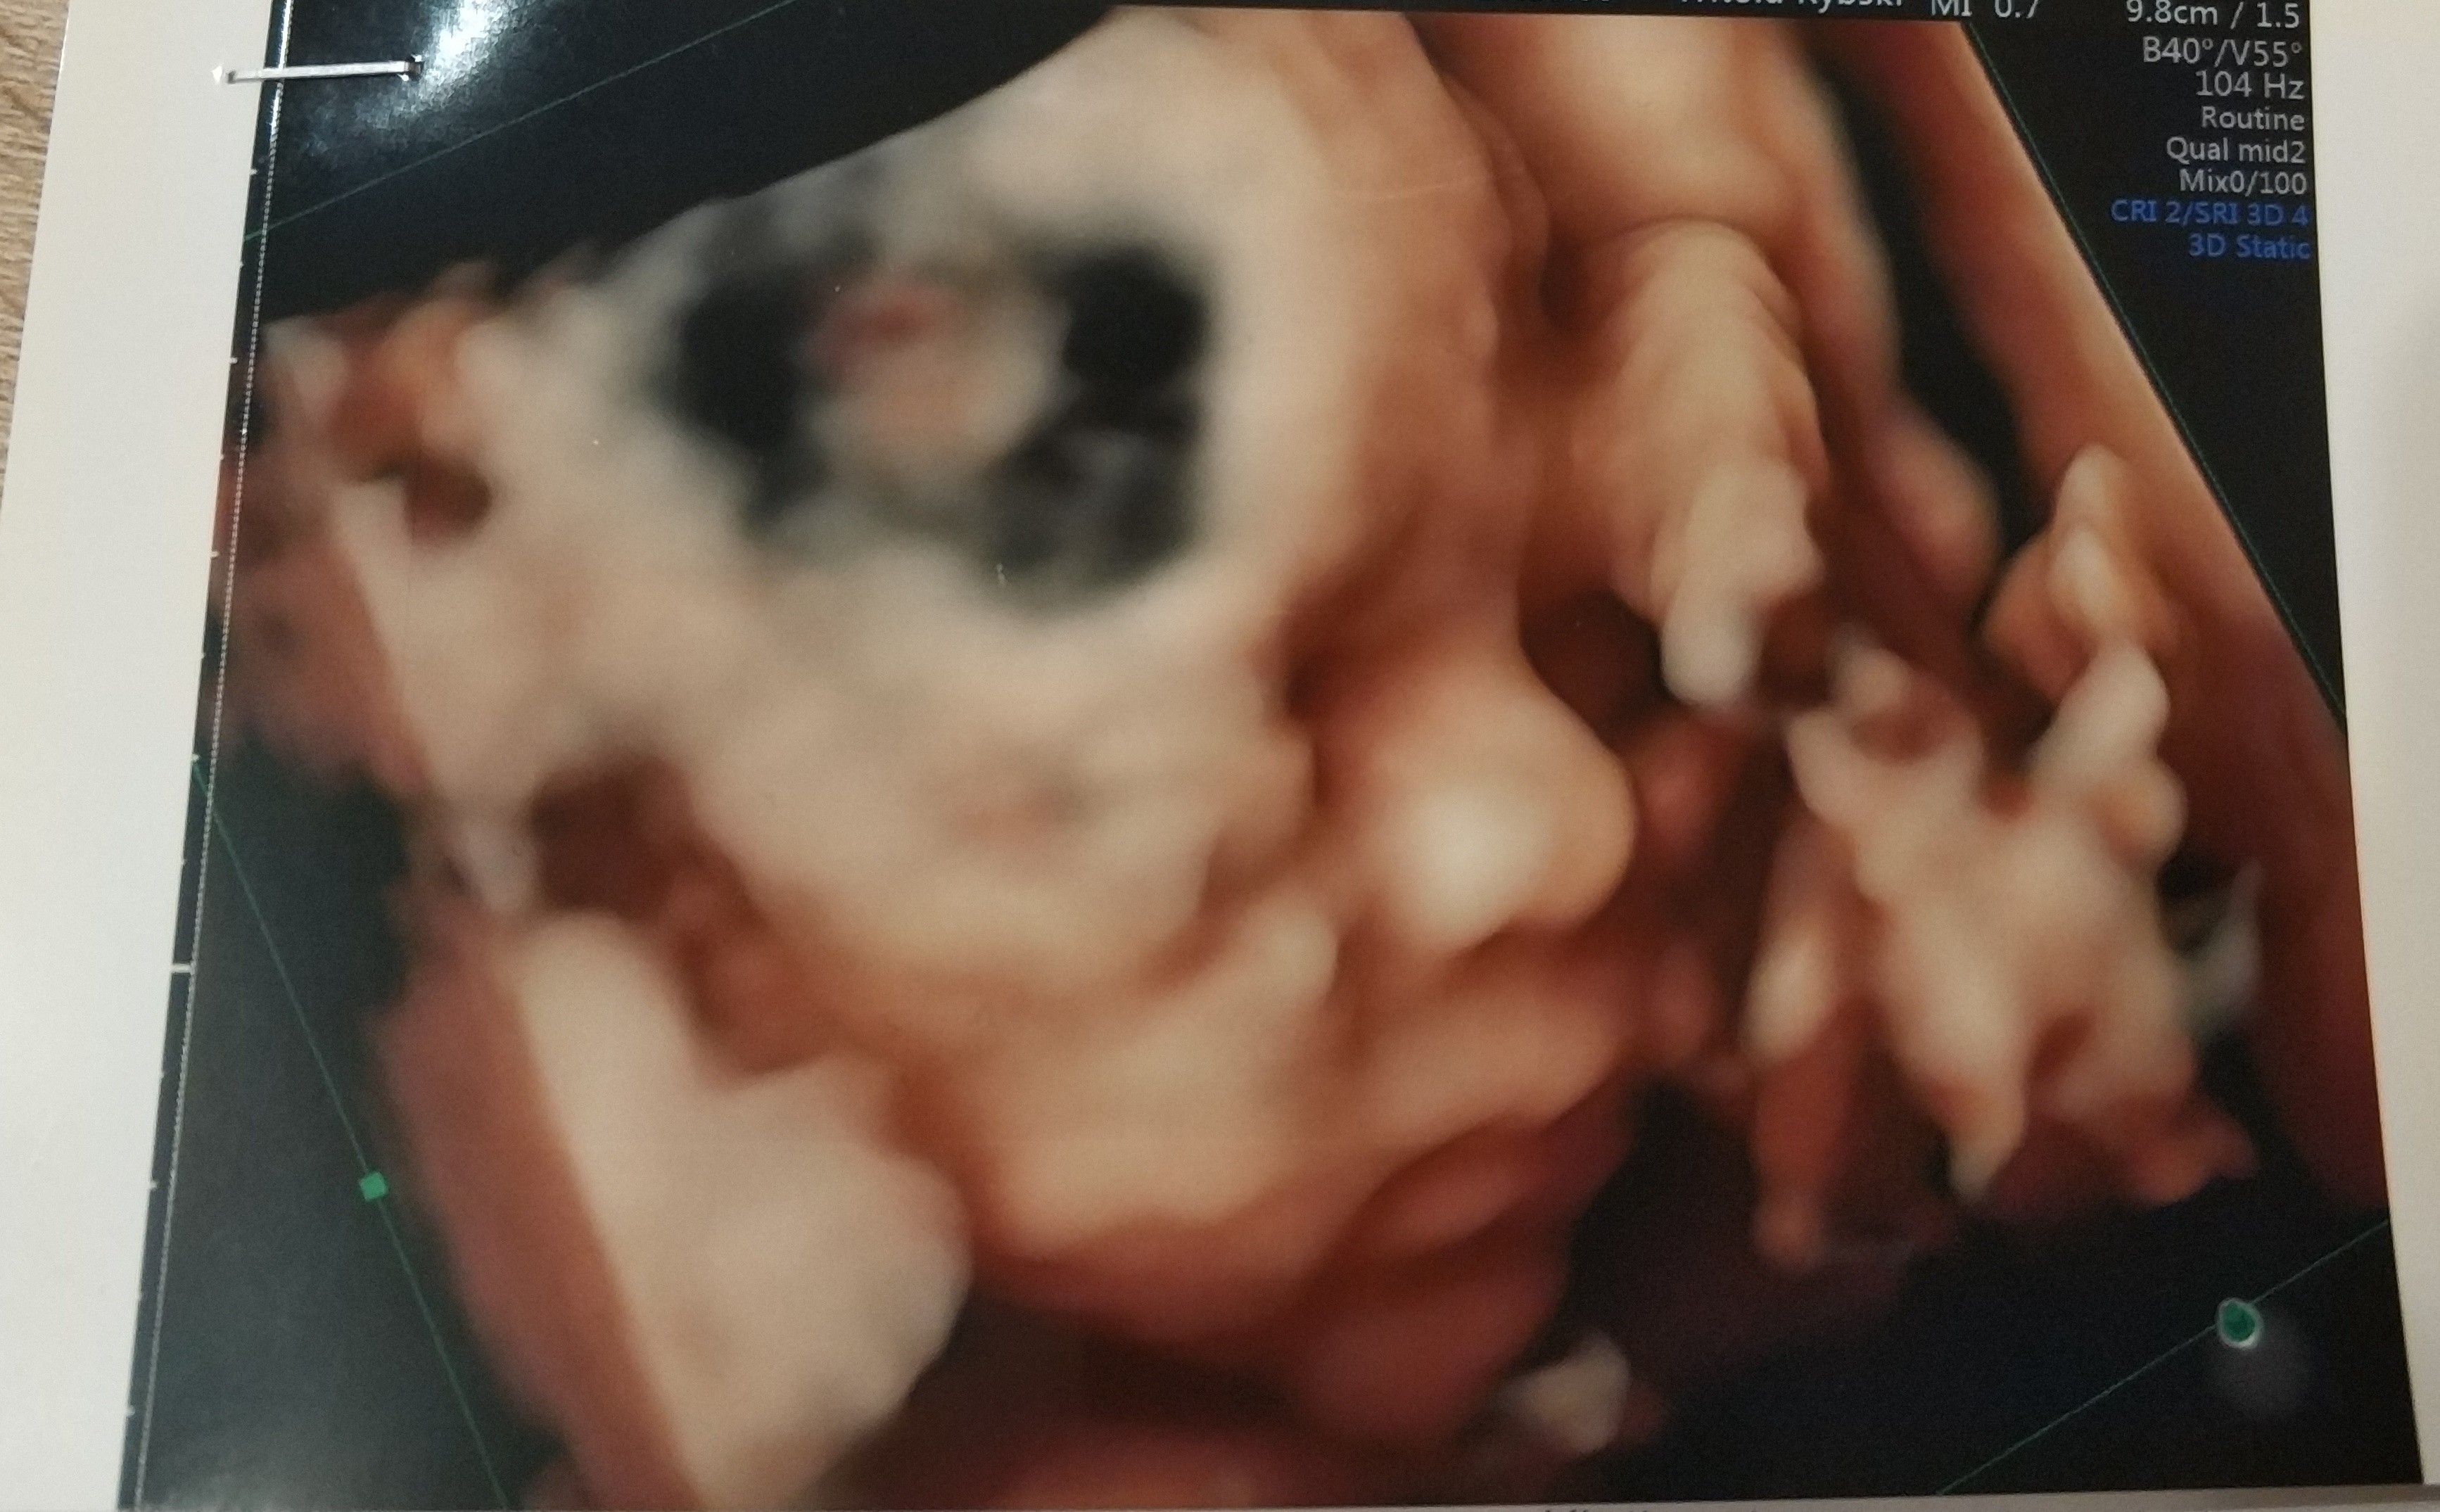

Hej. nie mialam kiedy napisac bo niedawno wrocilismy do domu.

Z synkiem wszystko jest super.

lekarz nie doszukal sie zadnej wady narzadów czy genetycznych.

Synus rosnie w siłę i odpowiada 25tc. Ogolnie kazal skontrolowac za 7-9 tyg. wage dziecka bo wyglada na to ze bedzie spory. do tego ulozony na poczatku posladkowo a finalnie poprzecznie. to sie moze z milion razy zmienic ale niezly kombinator z niego. Pan doktor zaznaczyl nam na usg siusiaczka nazywajac go armatką i ze na pewno bedzie straszyl kolezanki w przedszkolu :p

na zdj wyglada jak nasza corcia gdy sie urodzila :p wazy juz 700g :P